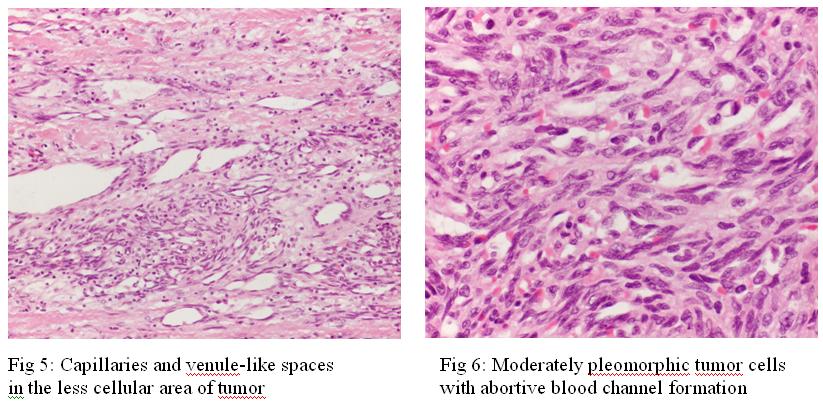

The atrial tumour was fleshy with extensive hemorrhage. Heterogeneous pattern was found on microscopic examination. There was abnormal blood space with feature of malignancy (Fig. 5 & 6). The CD31 and CD34 staining were positive while the HHV8 staining was negative. It was compatible with angiosarcoma.

The tumour can be dark red, hemorrhagic and lobular or diffusely infiltrate the pericardium and myocardium. Invasion of the superior and inferior vena cava, pulmonary artery and aortic root is not uncommon. Microscopically, the tumour shows vasoforming vascular channels lined by pleomorphic and atypical cells, and formation of irregular anastomosing sinusoidal structures with papillary intraluminal tufting. Immunohistochemically, the tumour has positive staining for factor VIII-related antigen, vimentin, CD34 and CD31.